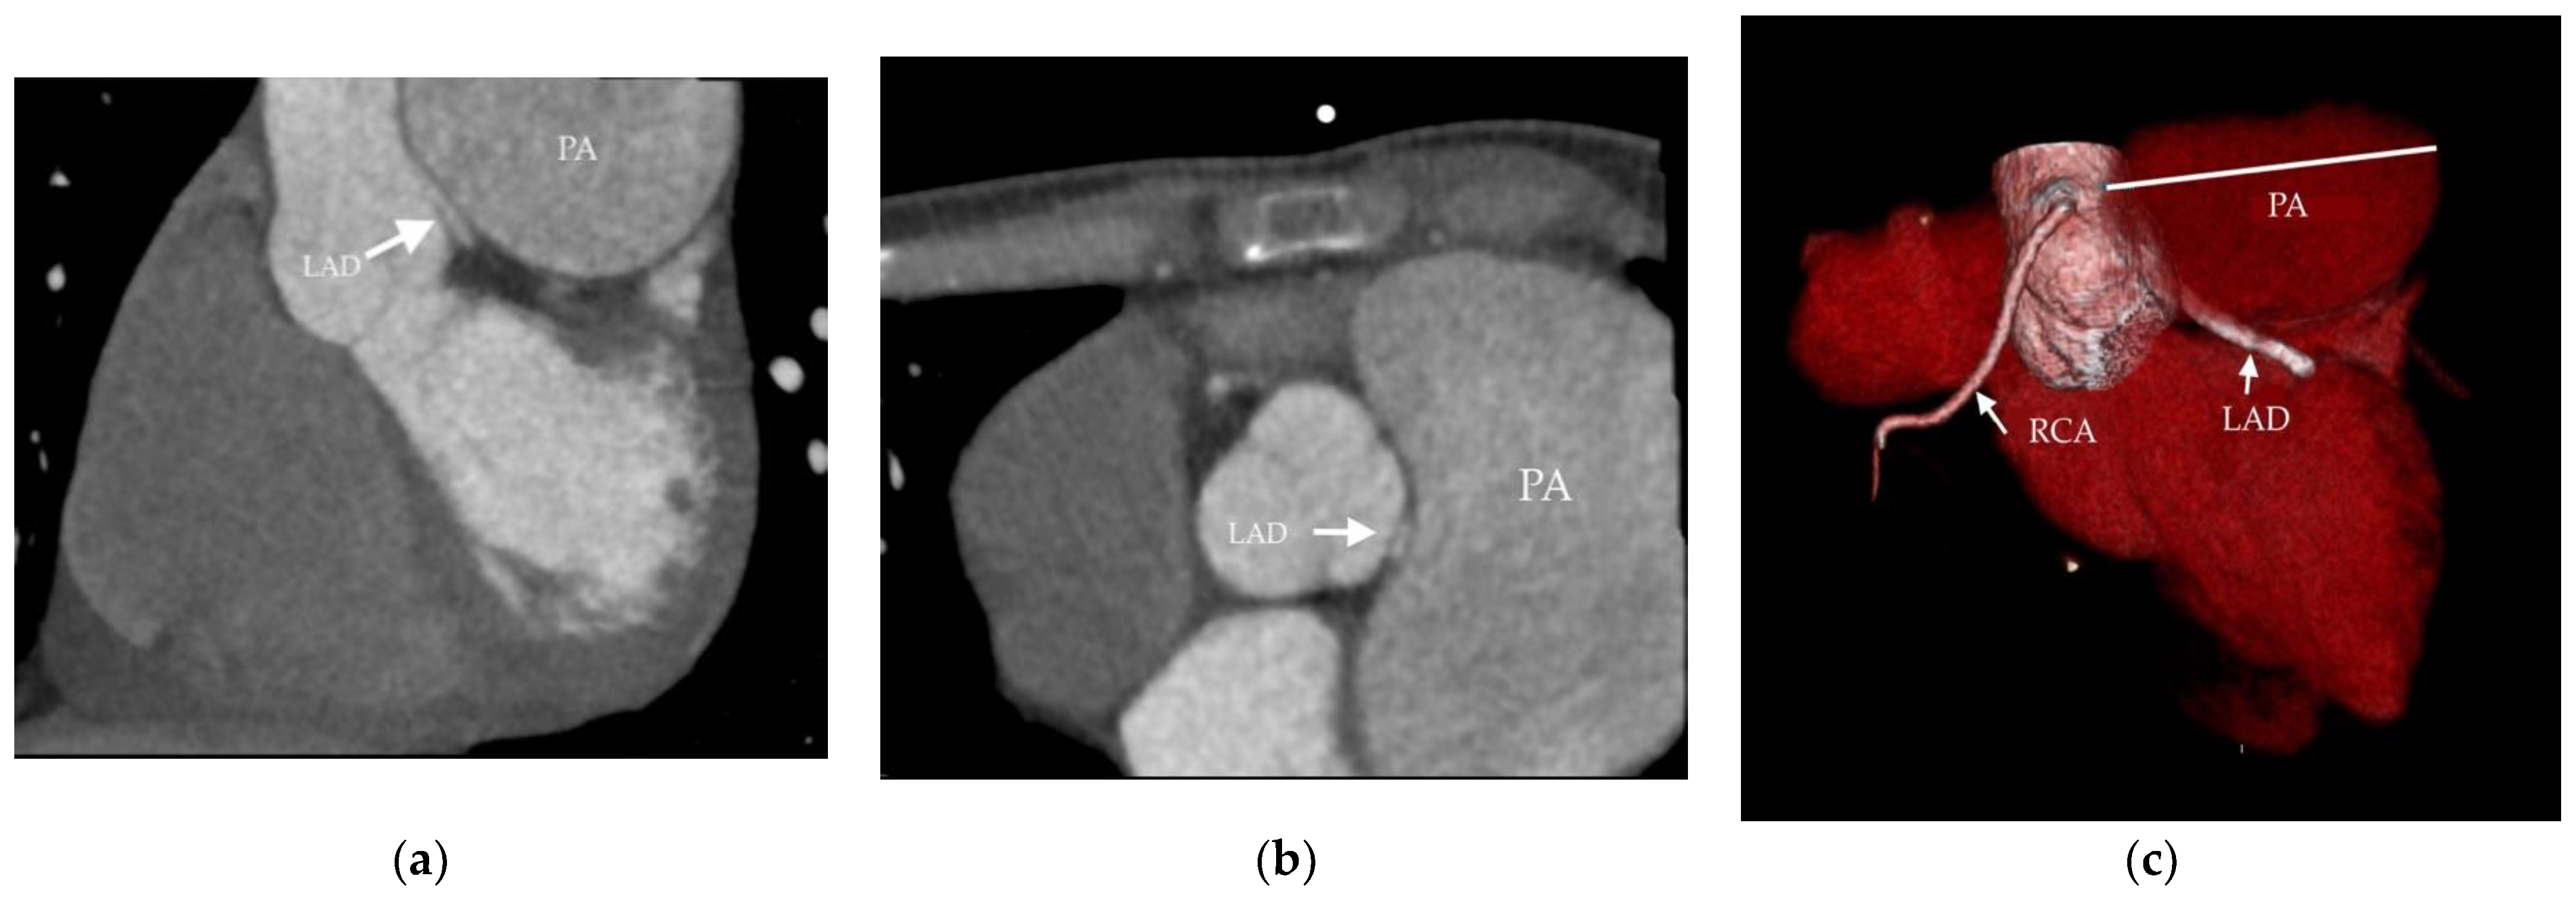

- Akbal, O.Y.; Kaymaz, C.; Tanboga, I.H.; Hakgor, A.; Yilmaz, F.; Turkday, S.; Dogan, C.; Tanyeri, S.; Demir, D.; Bayram, Z.; et al. Extrinsic Compression of Left Main Coronary Artery by Aneurysmal Pulmonary Artery in Severe Pulmonary Hypertension: Its Correlates, Clinical Impact, and Management Strategies. Eur. Heart J. Cardiovasc. Imaging 2018, 19, 1302–1308. [Google Scholar] [CrossRef]

- Hernández, V.; Ruiz-Cano, M.J.; Escribano, P.; Sánchez, M.A. Complications of Proximal Pulmonary Artery Aneurysm in Patients with Severe Pulmonary Arterial Hypertension. Rev. Esp. Cardiol. 2010, 63, 617–618. [Google Scholar] [CrossRef]

- Caldera, A.E.; Cruz-Gonzalez, I.; Bezerra, H.G.; Cury, R.C.; Palacios, I.F.; Cockrill, B.A.; Inglessis-Azuaje, I. Endovascular Therapy for Left Main Compression Syndrome. Case Report and Literature Review. Chest 2009, 135, 1648–1650. [Google Scholar] [CrossRef]

- Galiè, N.; Saia, F.; Palazzini, M.; Manes, A.; Russo, V.; Bacchi Reggiani, M.L.; Dall’Ara, G.; Monti, E.; Dardi, F.; Albini, A.; et al. Left Main Coronary Artery Compression in Patients With Pulmonary Arterial Hypertension and Angina. J. Am. Coll. Cardiol. 2017, 69, 2808–2817. [Google Scholar] [CrossRef]